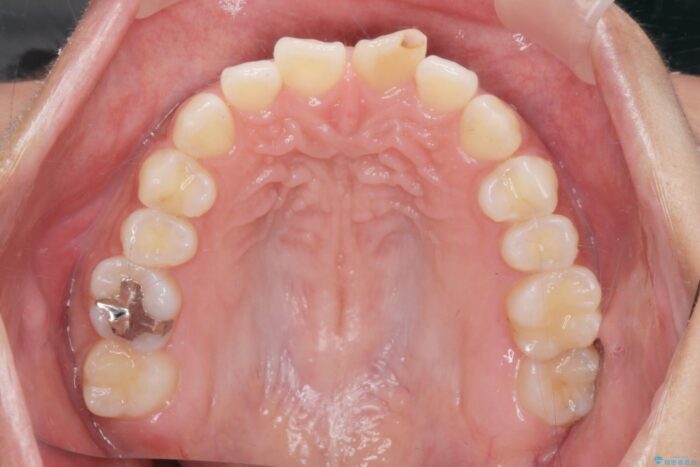

噛まない前歯と捻じれてしまった歯を改善したいと、矯正治療を希望された患者様です。

マルチブラケットを用いた非抜歯のワイヤー矯正で噛み合わせと歯並びを改善していきます。